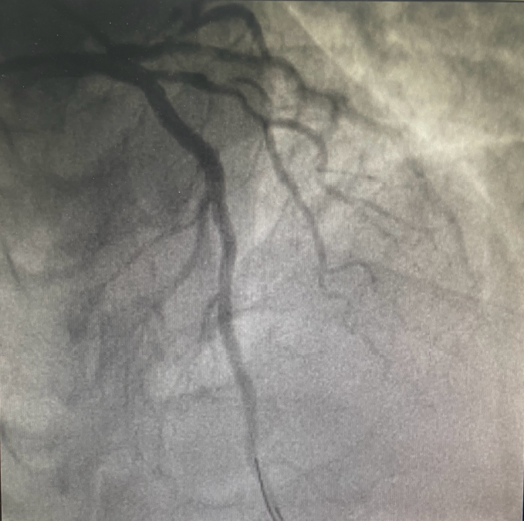

23:43分

于前降支近至中段、病变处植入支架2枚,手术治疗完成。

23:48分

患者胸痛症状缓解,生命体征平稳,送至CCU病房进一步治疗。

血管开通后

我院胸痛中心团队同心协力、高效配合,为患者实行“双绕行”绿色抢救通道,由“120”直接将患者送入导管室,实现了院前急救到医院抢救的无缝衔接。在最短的时间内使得患者闭塞的血管恢复畅通,从患者到达医院至导丝通过(简称D2W),门丝时间用时13分钟,远远低于国家胸痛中心要求的90分钟。从穿刺开始到手术结束也仅用18分钟!为患者的抢救争取了宝贵时间,大大提高了心梗患者的生存率、降低致死率。